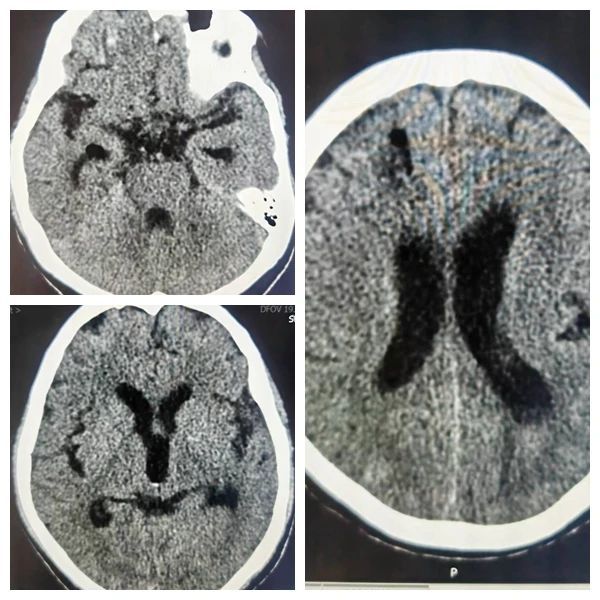

立即行CT检查

患者头颅CT可见广泛的蛛网膜下腔出血及脑室积血